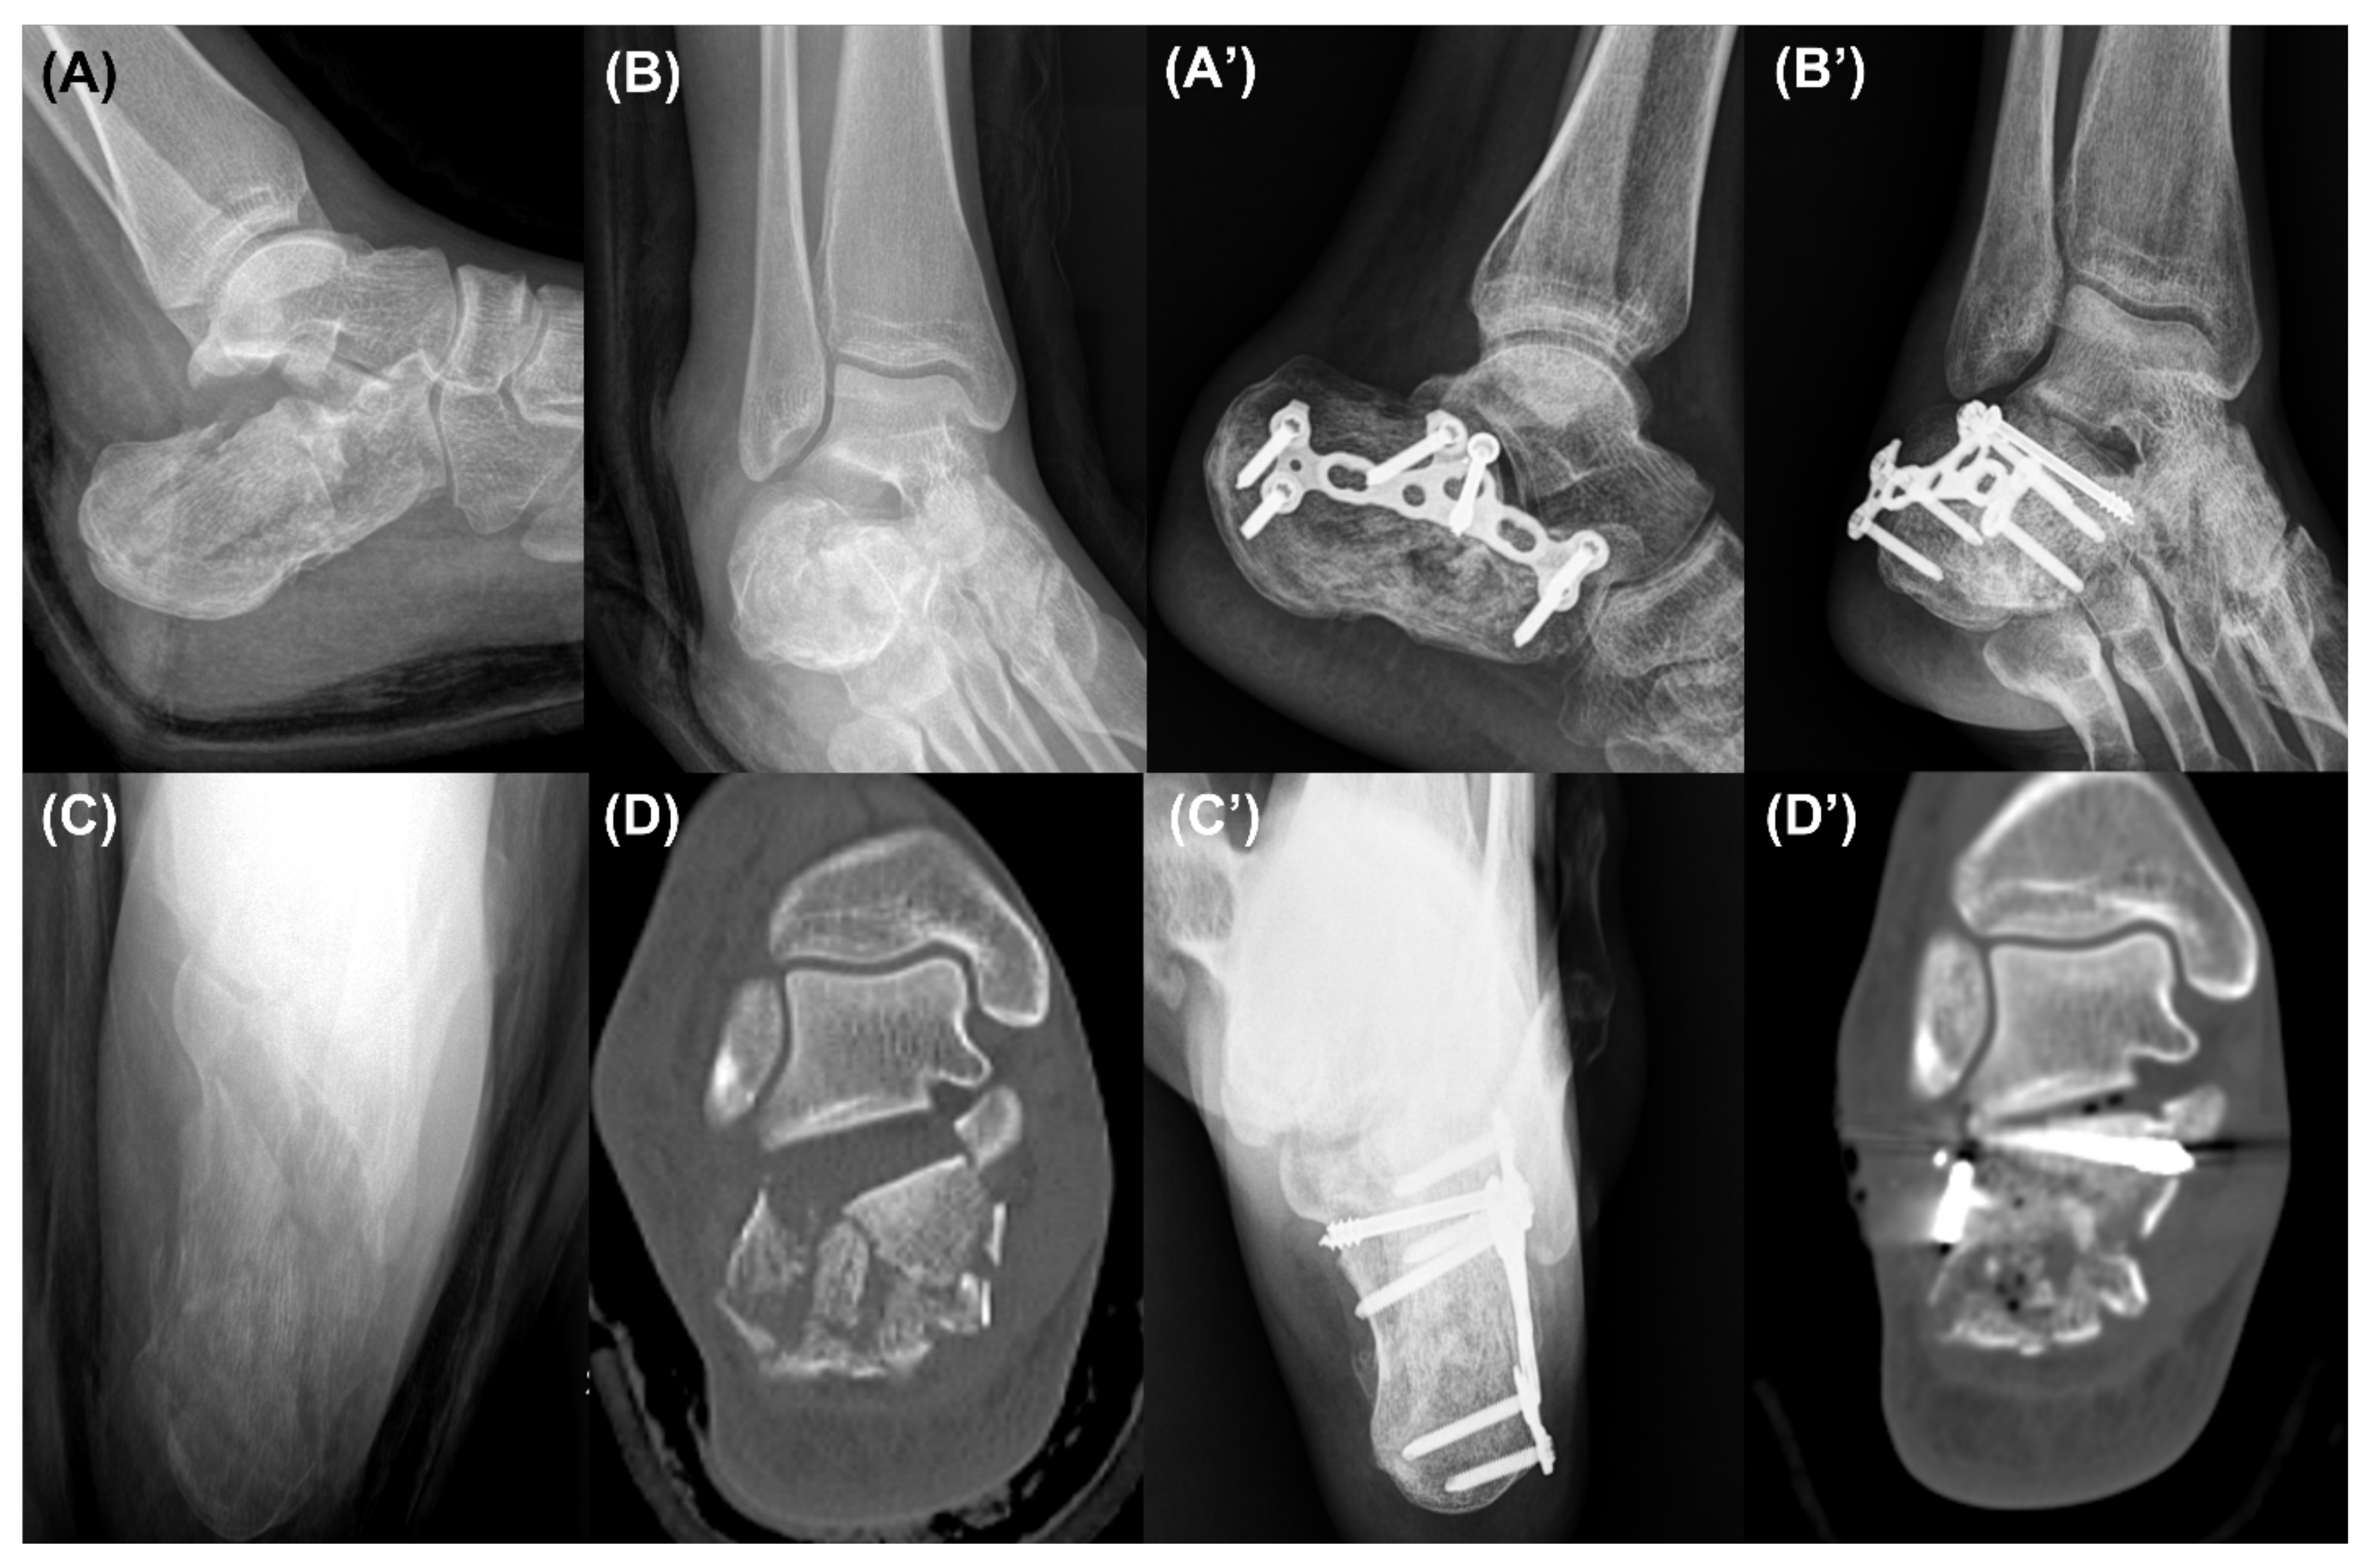

2.2. Surgical Technique